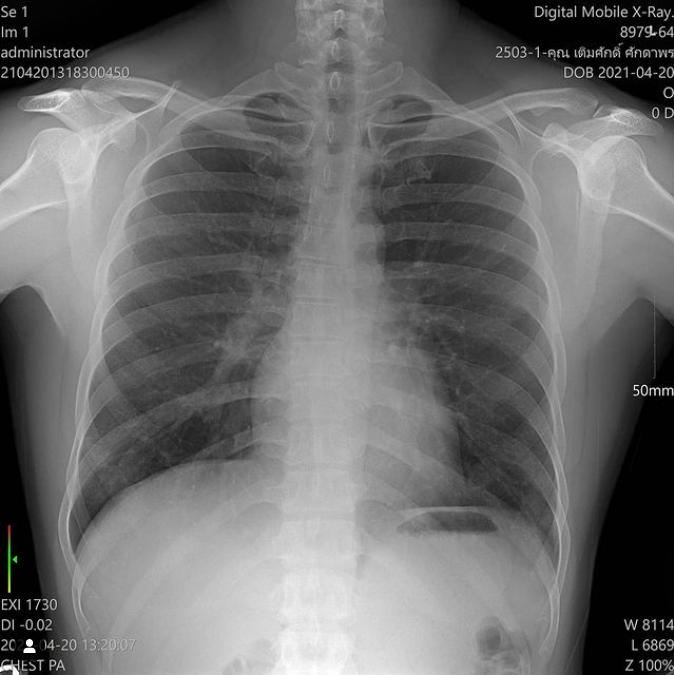

นอกจากนี้ อีฟยังได้โพสต์ภาพฟิลม์ x-ray ปอดของสามีด้วย พร้อมแคปชั่น

“X ray ปอดคุณสามี หมอแจ้งว่ามีฝ้าที่ปอดทั้งสองข้าง (แม่ดูไม่เป็น) แปลว่าเชื้อเริ่มลงปอดแล้ว และจะต้องย้ายตัวไปให้ยาที่รพ. พรุ่งนี้รถพยาบาลจะมารับป่าป๊าไป ก็จะเหลือแม่กับลูกอยู่กันสองคนที่ Hospitel ป่าป๊าบอกว่าไม่รู้จะนอนหลับไม๊เพราะกลัวผี แม่เลยบอกว่าขอยานอนหลับหมอเลยถ้านอนไม่หลับเพราะป่าป๊าจะต้องรีบหาย จะได้กลับบ้านพร้อมกันนะ ป่าป๊าสู้ๆ ทุกคนในครอบครัวเราต้องสู้ๆ คุณตายังสู้เลย เราจะจับมือผ่านโรคบ้าๆนี่ไปด้วยกัน เมื่อผ่านเรื่องนี้ไปแล้ว เราจะรู้ว่าครอบครัวเราแข็งแรงและเป็นอันหนึ้งอันเดียวกันแค่ไหนเมื่อต้องเจอเรื่องร้ายๆ”

“ต้นนะคะ สามี ได้ทราบผล x-ray วันนี้ จริง ๆ ต้นเนี่ยไม่ได้มีอาการอะไรเลย ไม่มีไข้ มีเสมหะในคอแต่ก็ไม่ไอ แต่ผล x-ray ออกมาว่าปอดมีฝ้า เห็นเป็นฝ้า ๆ สองข้าง คุณหมอบอก ต้องไปให้ยาต้านที่โรงพยาบาล พรุ่งนี้โรงพยาบาลก็จะมารับต้นไป ส่วนอีฟกับมีบุญก็จะยังอยู่ที่เดิมต่อไป”